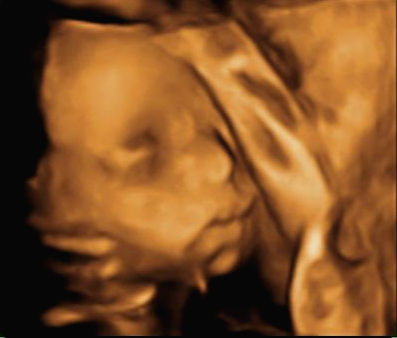

그리고 초음파 봐주시는 분께서 13주차가 되면 정확히 알 수 있으니 다음 주에 오라고 하셔서 일주일 뒤 다시 방문을 했습니다. (위에 사진은 12주 차 때 아들이라고 보여주신 초음파 사진이에요~ 화살표 보면 툭 튀어나와있는 부분을 보여주면서 아들이라고 하셨어요~)

입체 초음파 사진은 항상 만족스러워요! 사진 보면 벌써 태어난 아기처럼 어찌 이리 이목구비 뚜렷하고 아이 얼굴이 선명하게 잘 보이는지~ 제아이라 이렇게 사랑스러운 걸까요~? ㅋㅋㅋ

내 뱃속에 이렇게 사랑스러운 아이가 있다니 >. < 이렇게 이쁜 아이를 보면 성별반전은 중요하지 않아요~